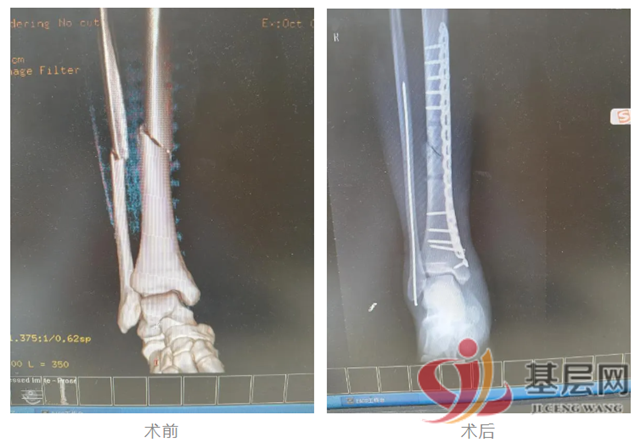

十一国庆假期期间,李师傅儿子在打篮球时摔伤右小腿,当即入湘乡某医院就诊,诊断为右胫腓骨骨折,被告知需手术治疗。因手术为择期手术,只能安排在国庆假期之后。由于患者在外地上学,怕耽误学习,李师傅慕名找到该院骨一科住院治疗。为尽量不耽误患者的学业,正在休假的付敏主任放弃休假,组织医师团队对患者进行及时的诊断和术前评估,并与手术室、麻醉科进行有效沟通,于10月2日成功为患者实施了胫腓骨骨折手术。经过一段时间的康复,患者病情痊愈出院,及时回到了学校,家属为了表达感激之情特意送来锦旗。